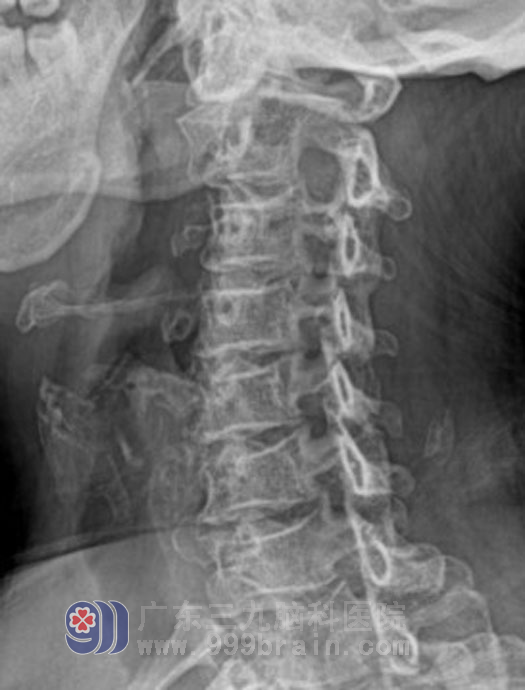

倪莹莹主任和邱承尧主治医生为她安排了针对性的临床检查,并请首席外科专家黄勤教授阅片把关排除垂体瘤复发。最后颈椎片的特异表现,引起了专家的注意,在第4-5颈椎右侧钩椎关节像鱼刺样变尖,相应椎间孔明显变窄,另外临床还有一个非常少见的特点,每当头痛发作病人通过进食一些热稀饭或热糊状食物,疼痛就能缓解,于是专家分析这是因为增生的骨刺反复刺激深部颈肌导致局部组织水肿,粘连,血管痉挛,而颈肌深部血管神经与咽喉相毗邻,口腔咽喉持久的温热刺激可以松解痉挛的血管和肌肉,从而缓解疼痛,思路明确了,就有了对策。

第4-5颈椎右侧钩椎关节像鱼刺样变尖

第4-5颈椎间孔明显变窄